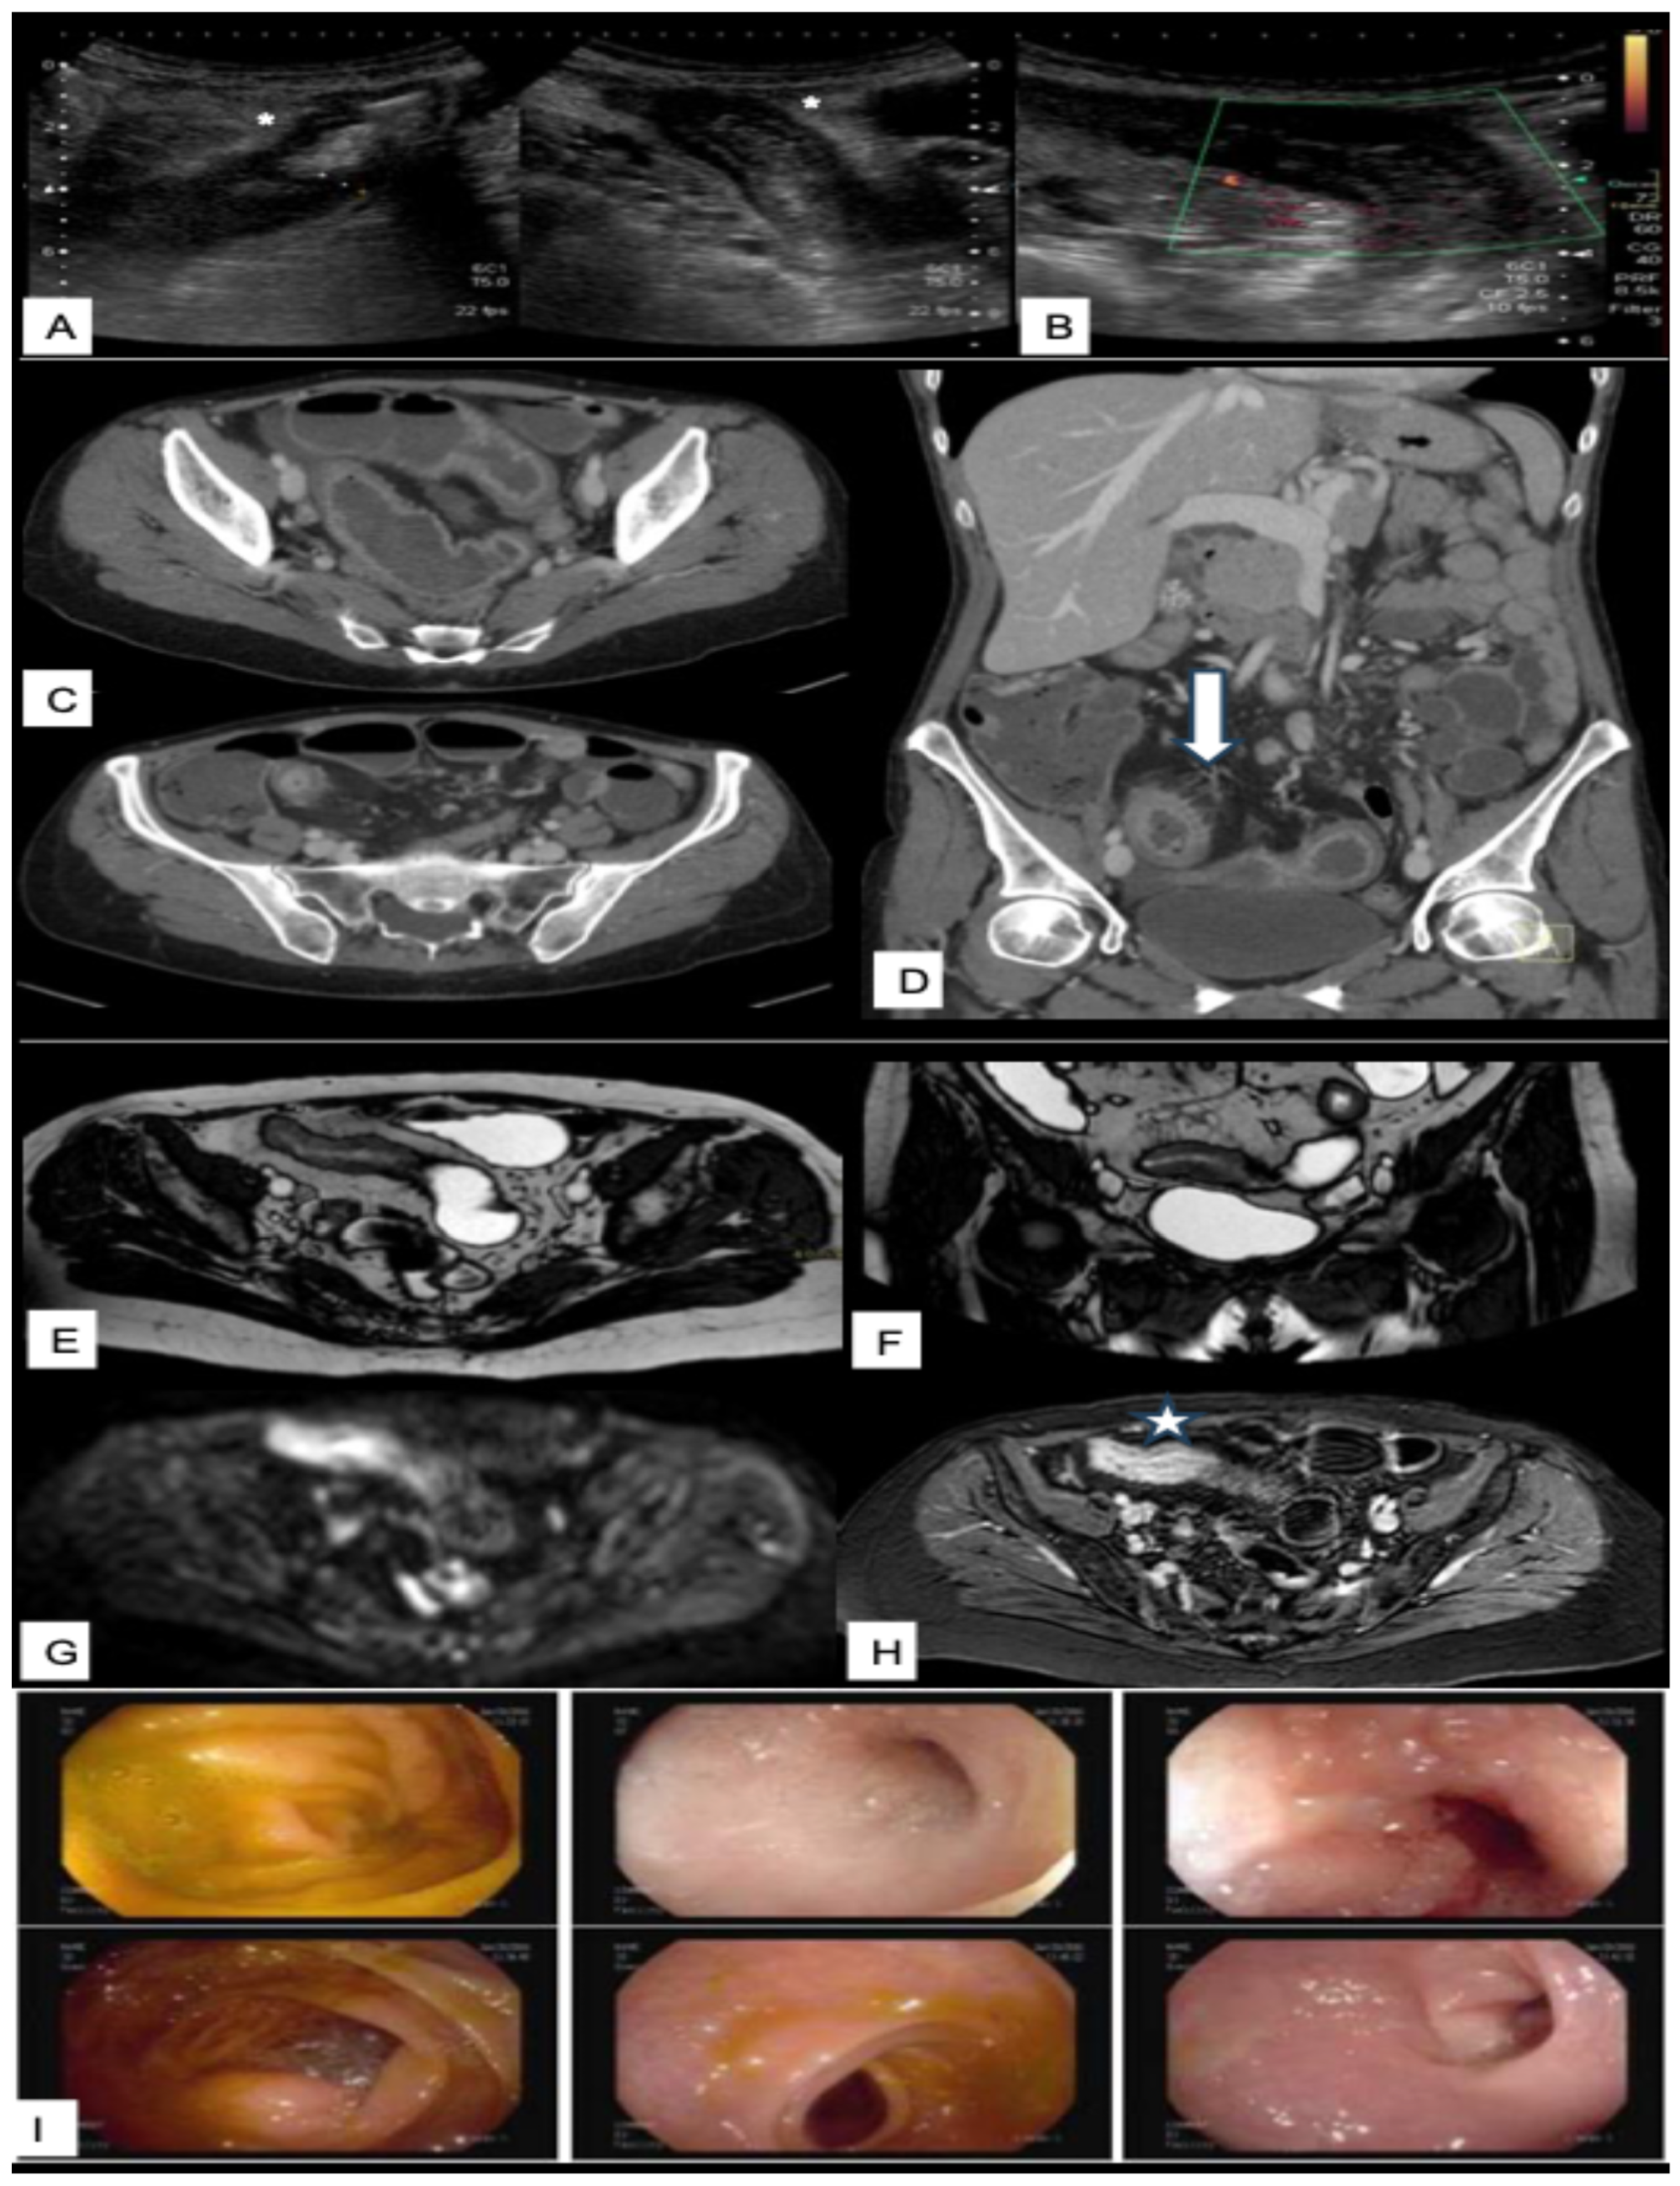

3.3. CT and CT Enterography

3.4.2. Typical MRI Findings in Crohn’s Disease

4. Intestinal Capsule Endoscopy